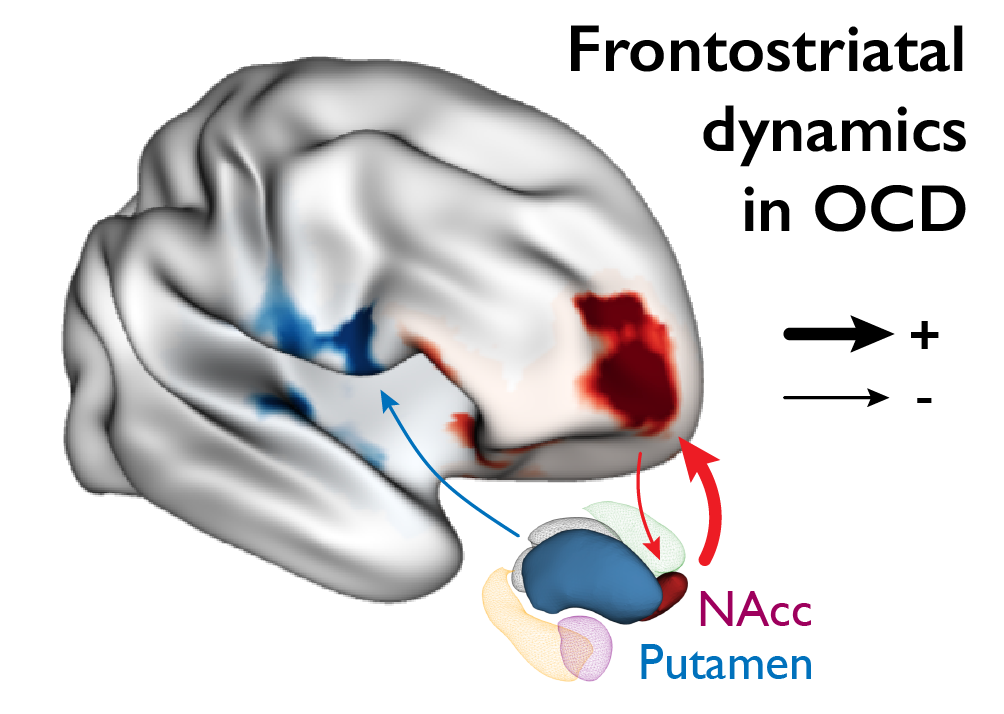

Data engineering, analysis of multimodal dataset, and multiscale modeling of neurostimulation in obsessive-compulsive disorders.